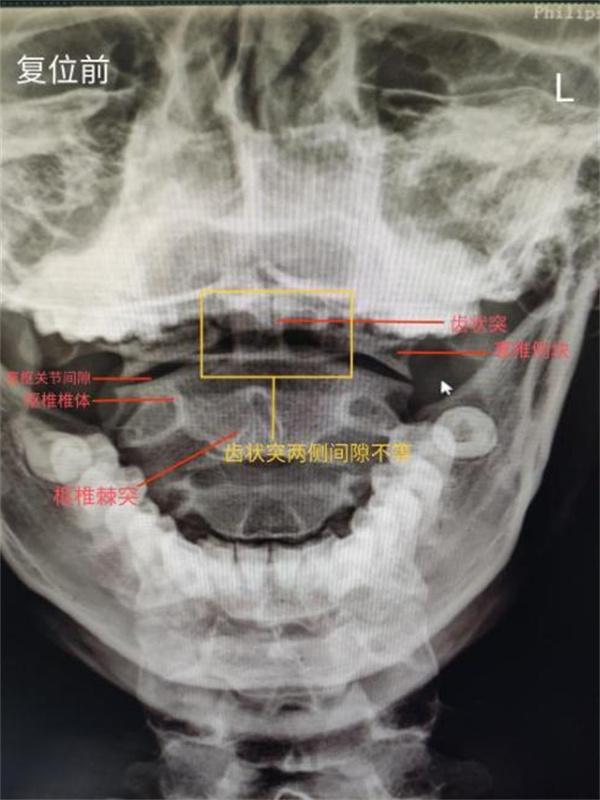

△ 复位前

推拿科接诊医师为进一步明确病因,仔细为小陈查体,摄片提示:双侧寰枢关节欠对称,齿状突欠居中,齿状突距左侧寰椎侧块 6mm 较右侧增宽 3mm。推拿科医师决定为行推拿正骨治疗。当场,小陈的 C2 双侧横突压痛消失。